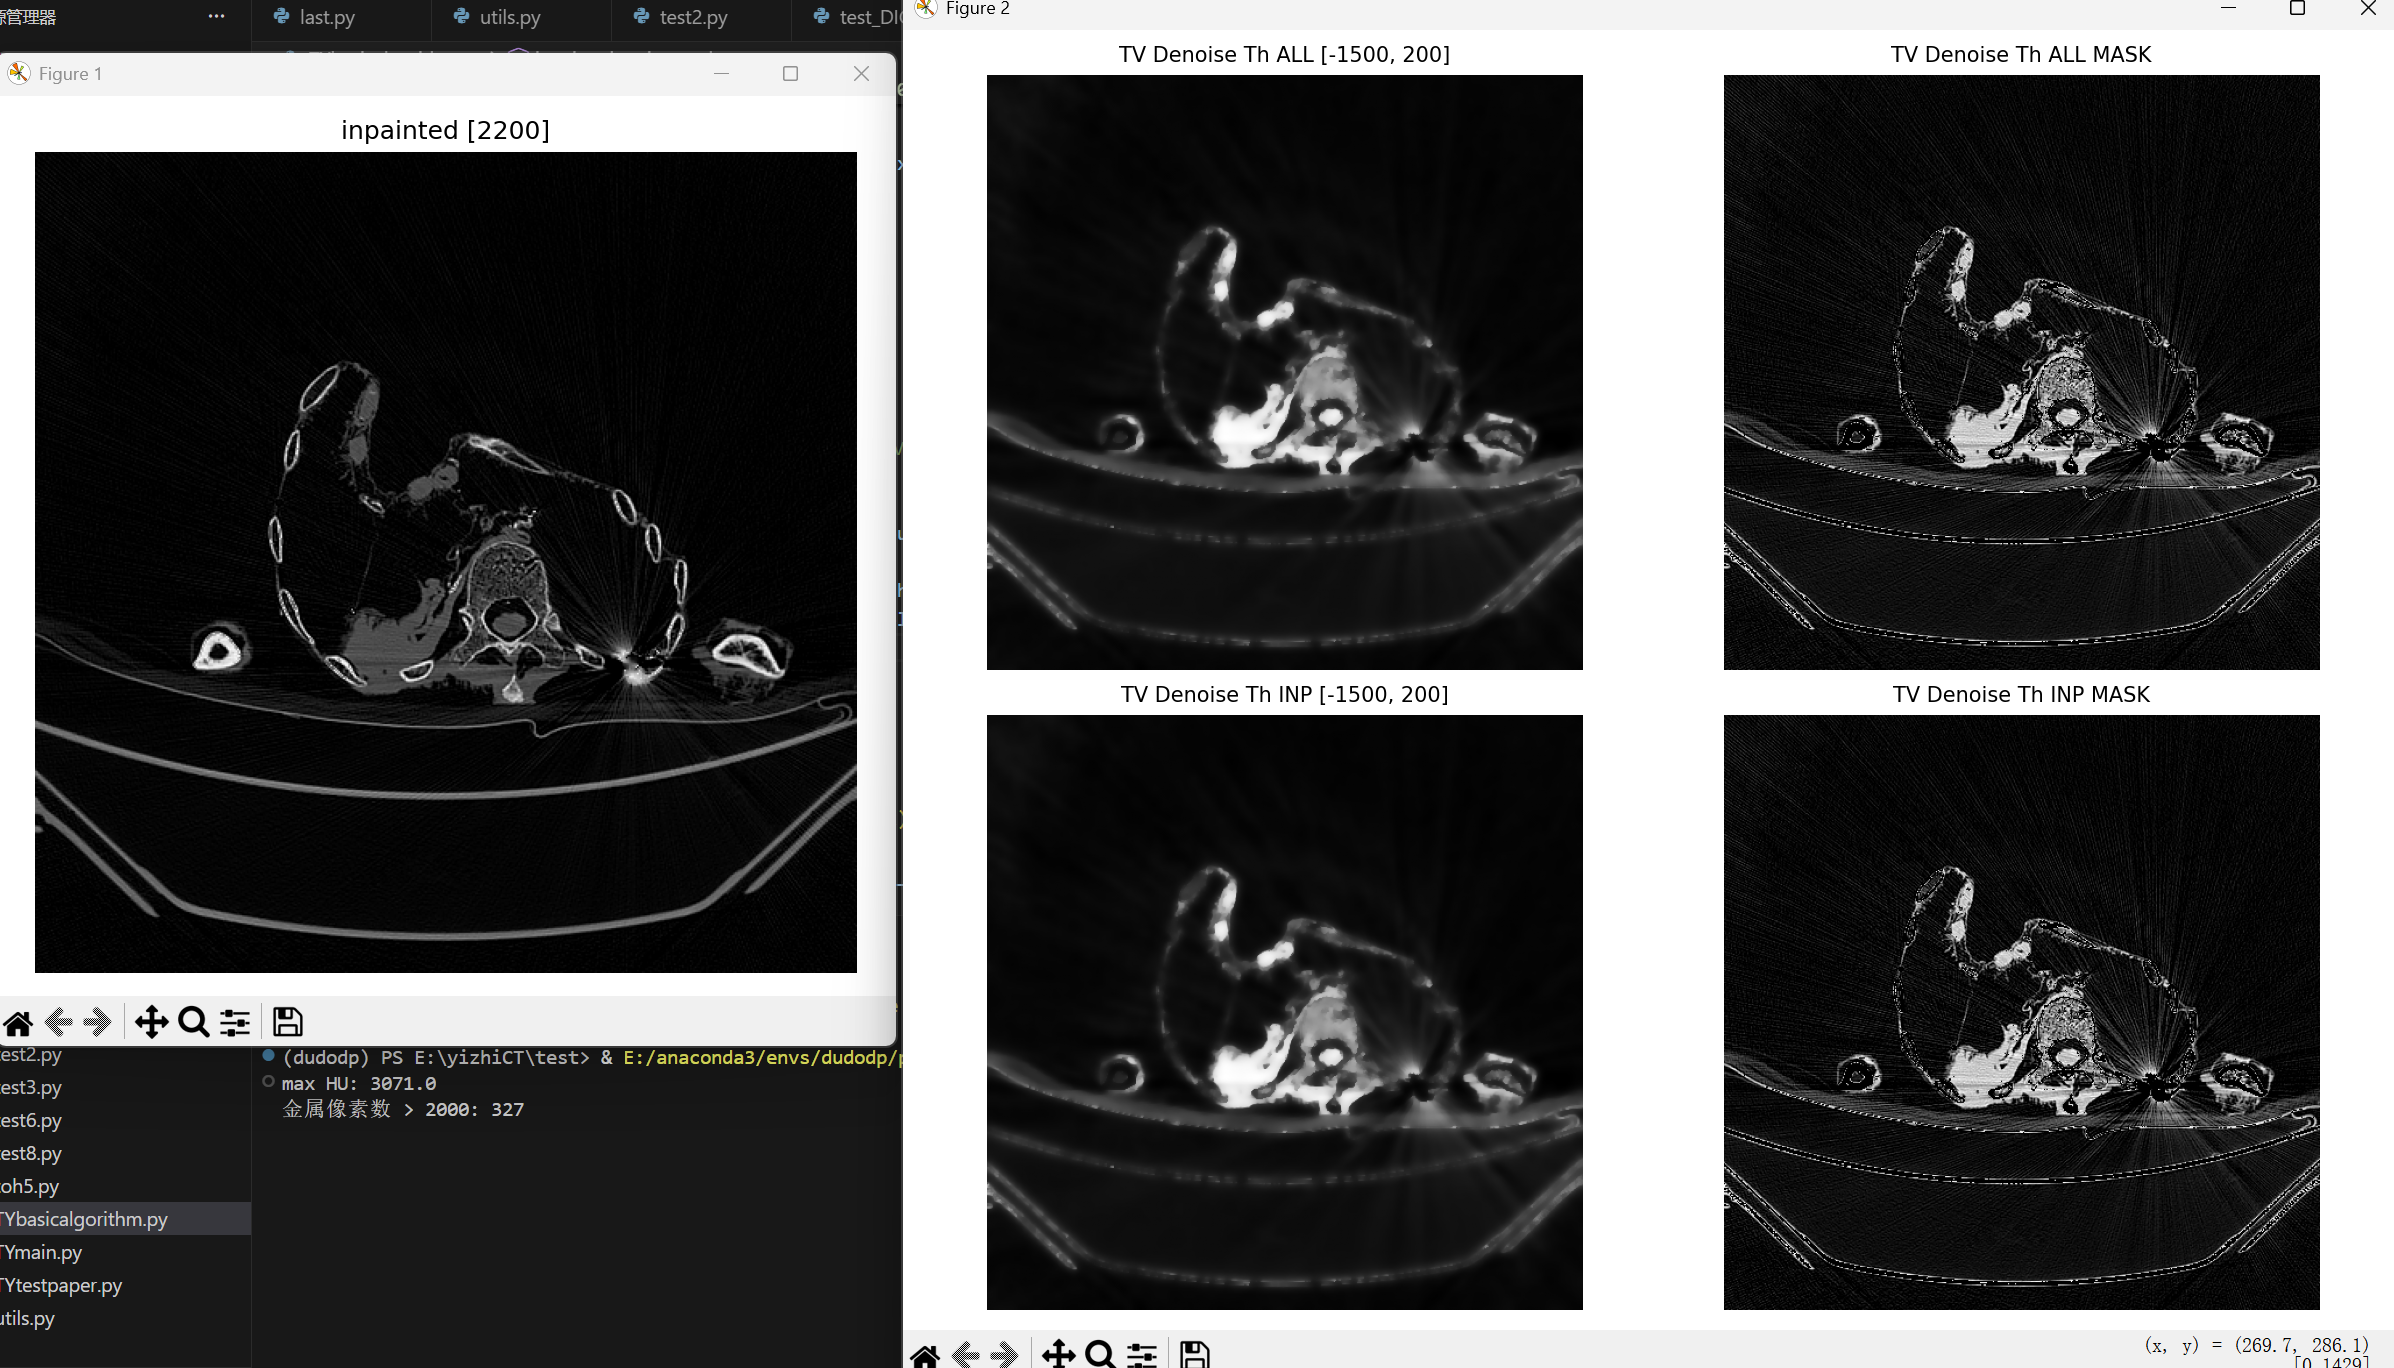

def inpaint_denoise_tv_th(ct_hu, hu_min=-1500, hu_max=200, weight=0.1, threshold=2200):

mask_in = extract_metal_mask(ct_hu, threshold=threshold)

inpainted = inpaint_opencv(ct_hu, mask_in)

plt.figure(figsize=(6, 6))

plt.imshow(inpainted, cmap='gray')

plt.title(f"inpainted [{threshold}]")

fig, axes = plt.subplots(2, 2, figsize=(10, 10)) # 两行三列

axes = axes.ravel()

axes[0].imshow(tv_black_all, cmap='gray')

axes[0].set_title(f"TV Denoise Th ALL [{hu_min}, {hu_max}]", fontsize=10)

axes[0].axis('off')

axes[1].imshow(tv_mask_all, cmap='gray')

axes[1].set_title(f"TV Denoise Th ALL MASK", fontsize=10)

axes[1].axis('off')

axes[2].imshow(tv_black_imp, cmap='gray')

axes[2].set_title(f"TV Denoise Th INP [{hu_min}, {hu_max}]", fontsize=10)

axes[2].axis('off')

axes[3].imshow(tv_mask_imp, cmap='gray')

axes[3].set_title(f"TV Denoise Th INP MASK", fontsize=10)

axes[3].axis('off')